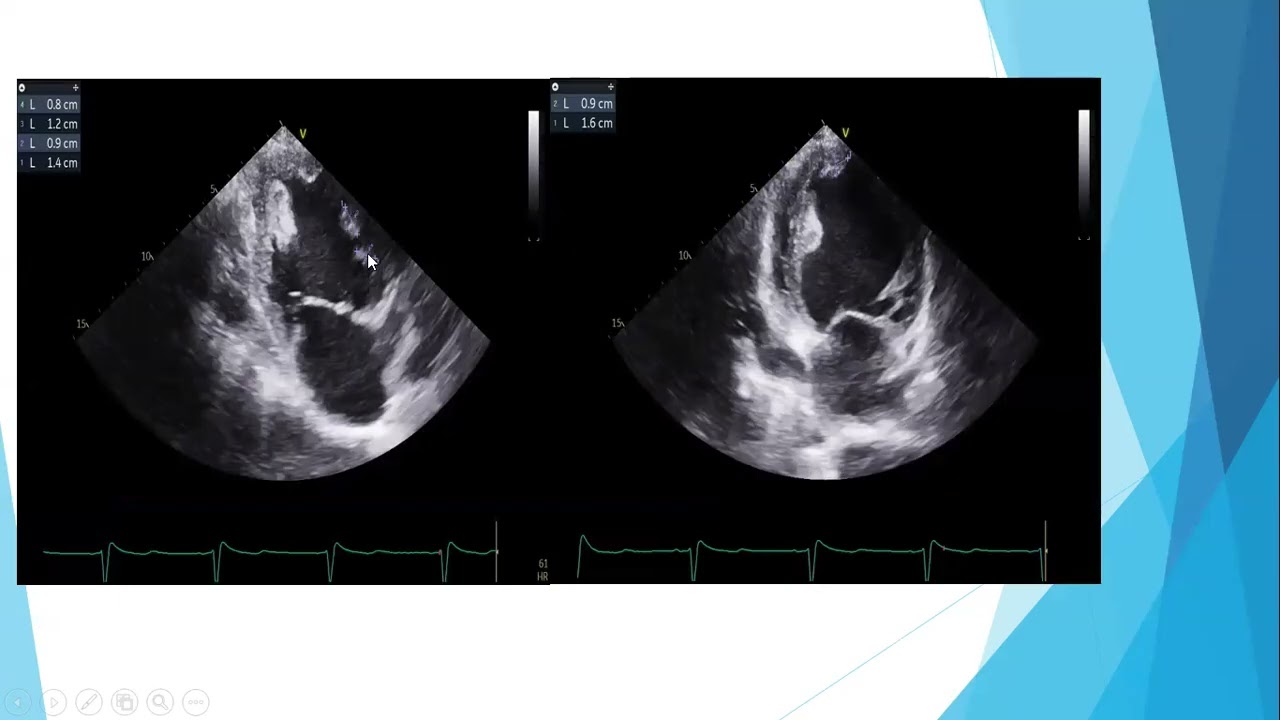

echo Conference 18/2 - Dr. Ramez leon - Metallic mitral valve prosthesis thrombus